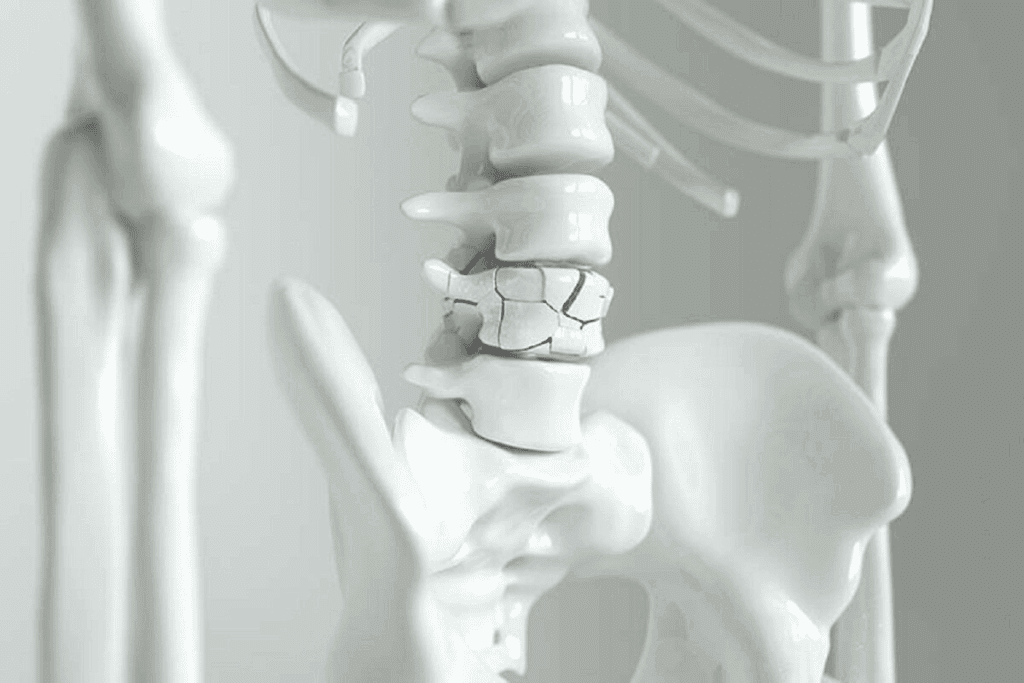

Another example is the intervertebral discs in the spine. These discs act as shock absorbers and let the spine move a little. They help keep the spine flexible and stable.

Symphysial joints can get sick. For example, the pubic symphysis can get osteitis pubis, which causes pain in the groin. Intervertebral discs can also herniate, leading to back pain.

“The integrity of symphysial joints is key for the skeletal system’s structure. Problems with these joints can cause a lot of pain and trouble.”